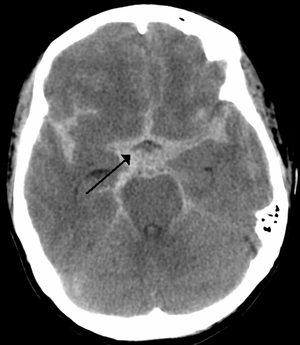

SAH presentation + RF

Sudden onset thunderclap headache, typically pulsates towards occiput

Can vomit or LOC

RF: berry aneurysms

Star shape on CT